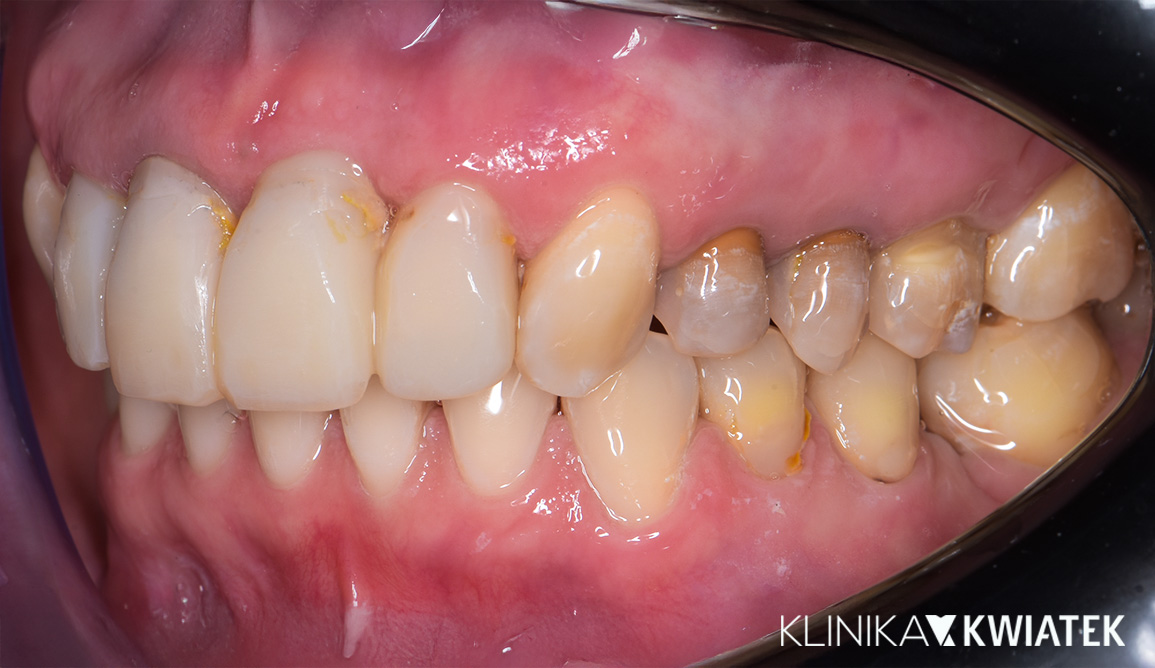

Odbudowa estetyczna - na zębach własnych i implantach

Pacjentka zgłosiła się z rozległymi brakami zębowymi oraz nieszczelnymi, nieestetycznymi pracami protetycznymi, które nie spełniały już swojej funkcji. Zależało jej na kompleksowej poprawie wyglądu uśmiechu, ale także na przywróceniu prawidłowej funkcji żucia i komfortu.

Zaplanowano wieloetapowe leczenie implantoprotetyczne, koncentrujące się na odbudowie braków oraz stabilizacji zwarcia. W trakcie terapii wykonano korony na implantach, pełnoceramiczne korony na zębach własnych oraz licówki ceramiczne – wszystko po to, by uzyskać naturalny efekt i funkcjonalną równowagę na długie lata.